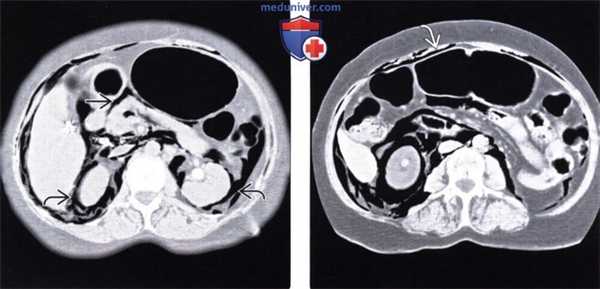

(Слева) На аксиальном КТ срезе (с контрастным усилением) у пожилого пациента, находящегося на вентиляции легких под давлением, с документированным двухсторонним пневмотораксом и пневмомедиастинумом, визуализируется газ, распространяющийся под давлением в брюшную полость, забрюшинное пространство и брыжейку.

(Справа) На аксиальном срезе (КТ с контрастом) у этого же пациента в дополнение к обширному скоплению газа в забрюшинном пространстве визуализируется газ в брюшной полости. В подобных случаях газ может распространяться в кишечной стенке, симулируя пневматоз в результате ишемии.